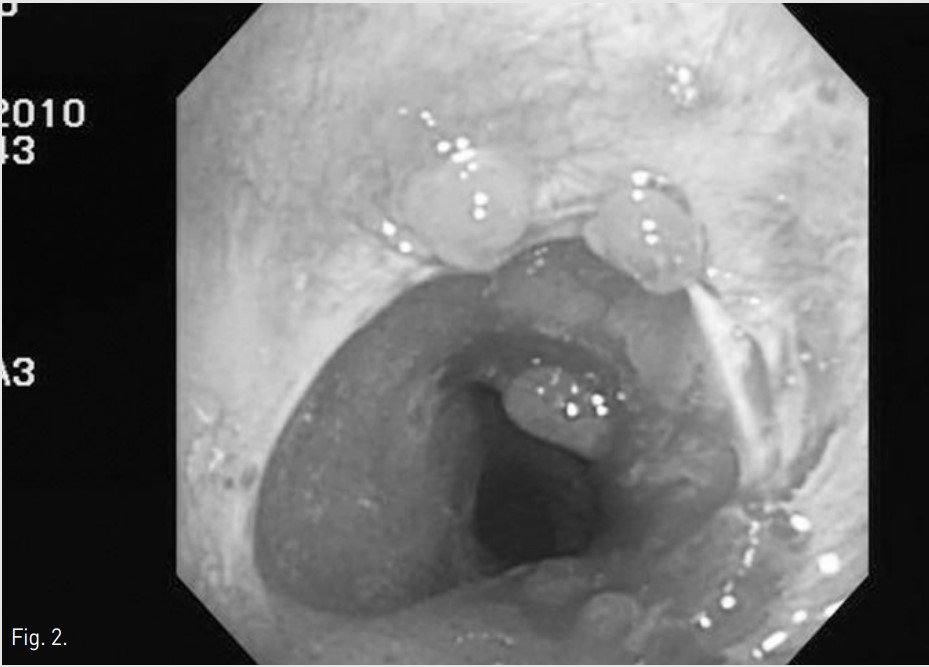

Fig. 2.

Fig. 2 Bronchoscopic image shows tracheal stenosis with multiple granulomatous lesions at upper trachea just below vocal cord level.